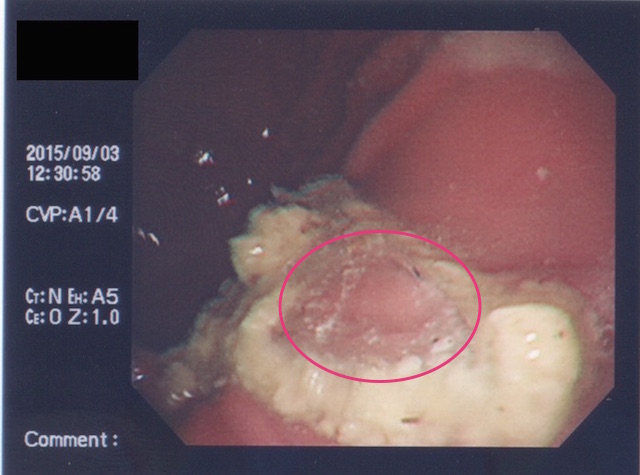

早速、内視鏡にて胃内を確認。すると、やはりありました。

しかも、ご丁寧に噛み砕かれていて複数個あります。。。(;´Д`)

内視鏡のポートより把持鉗子を挿入して異物を除去しながら、メガネのレンズのパズルをしていきました。無事パズル完成!!めでたしめでたし!!